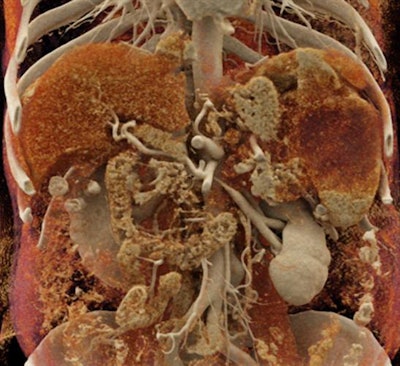

Cinematic rendering of an abdominal CT scan.In the current article, the group discussed three distinct ways in which cinematic rendering could facilitate the evaluation of a variety of conditions affecting the spleen, including the following:

- Neoplastic processes: The intrinsic ability of cinematic rendering to accentuate texture enables it to reveal spleen lymphomas, the organ's most common malignancy, more readily than standard CT -- thereby facilitating cancer diagnosis and prognosis, the authors noted. For rare tumors such as littoral cell angiomas, cinematic rendering can pinpoint underlying abnormalities that may help physicians distinguish between benign and malignant cases.

- Accessory spleen: Accessory splenic tissue seen on CT scans is occasionally mistaken for a tumor, especially for cancer patients. Standard CT and volume-rendered CT scans are often inadequate for determining tissue type in these cases and require a follow-up nuclear medicine exam to make a definitive diagnosis.

But cinematic rendering may obviate the need for additional testing in such cases because of the high level of soft-tissue detail it provides, as well as the pronounced differences it shows between the texture of tumor and normal tissue, according to the authors. "There may be tremendous opportunity to utilize this methodology to improve lesion characterization by visualization of texture within tumors and accessory splenic tissue," they wrote.

Cinematic rendering may provide surgeons with images that "better reflect intrinsic spatial relationships of structures within regions of complex anatomy," improve anatomical understanding for medical students and residents, bolster patient engagement, and even refine deep-learning algorithms, Fishman and colleagues wrote.